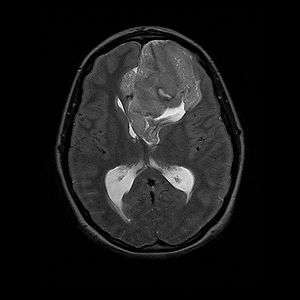

Neurocytoma

Neurocytoma (or neuroepithelioma) is a type of nervous system tumor which is primarily derived from nervous tissue.[1] This is in contrast to the gliomas (such as oligodendroglioma), which are derived from glial cells, which are not derived from nervous tissue.